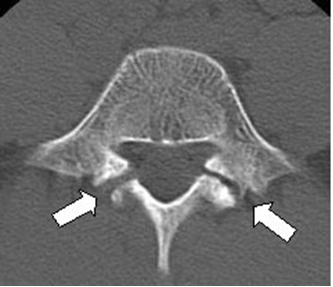

(腰椎を輪切りにしたCTの画像。)

CTでは,小さな骨折線でも明瞭に判断できますし、さらに MRIではCTではっきりする前の段階でも

腰椎の負担のかかっている部分に白く光る影が確認できるため、最も早く分離症を発見できます。

腰痛があって疑わしい場合は、ぜひ、レントゲンだけではなくMRIとCT検査を受けることを強く勧めます。